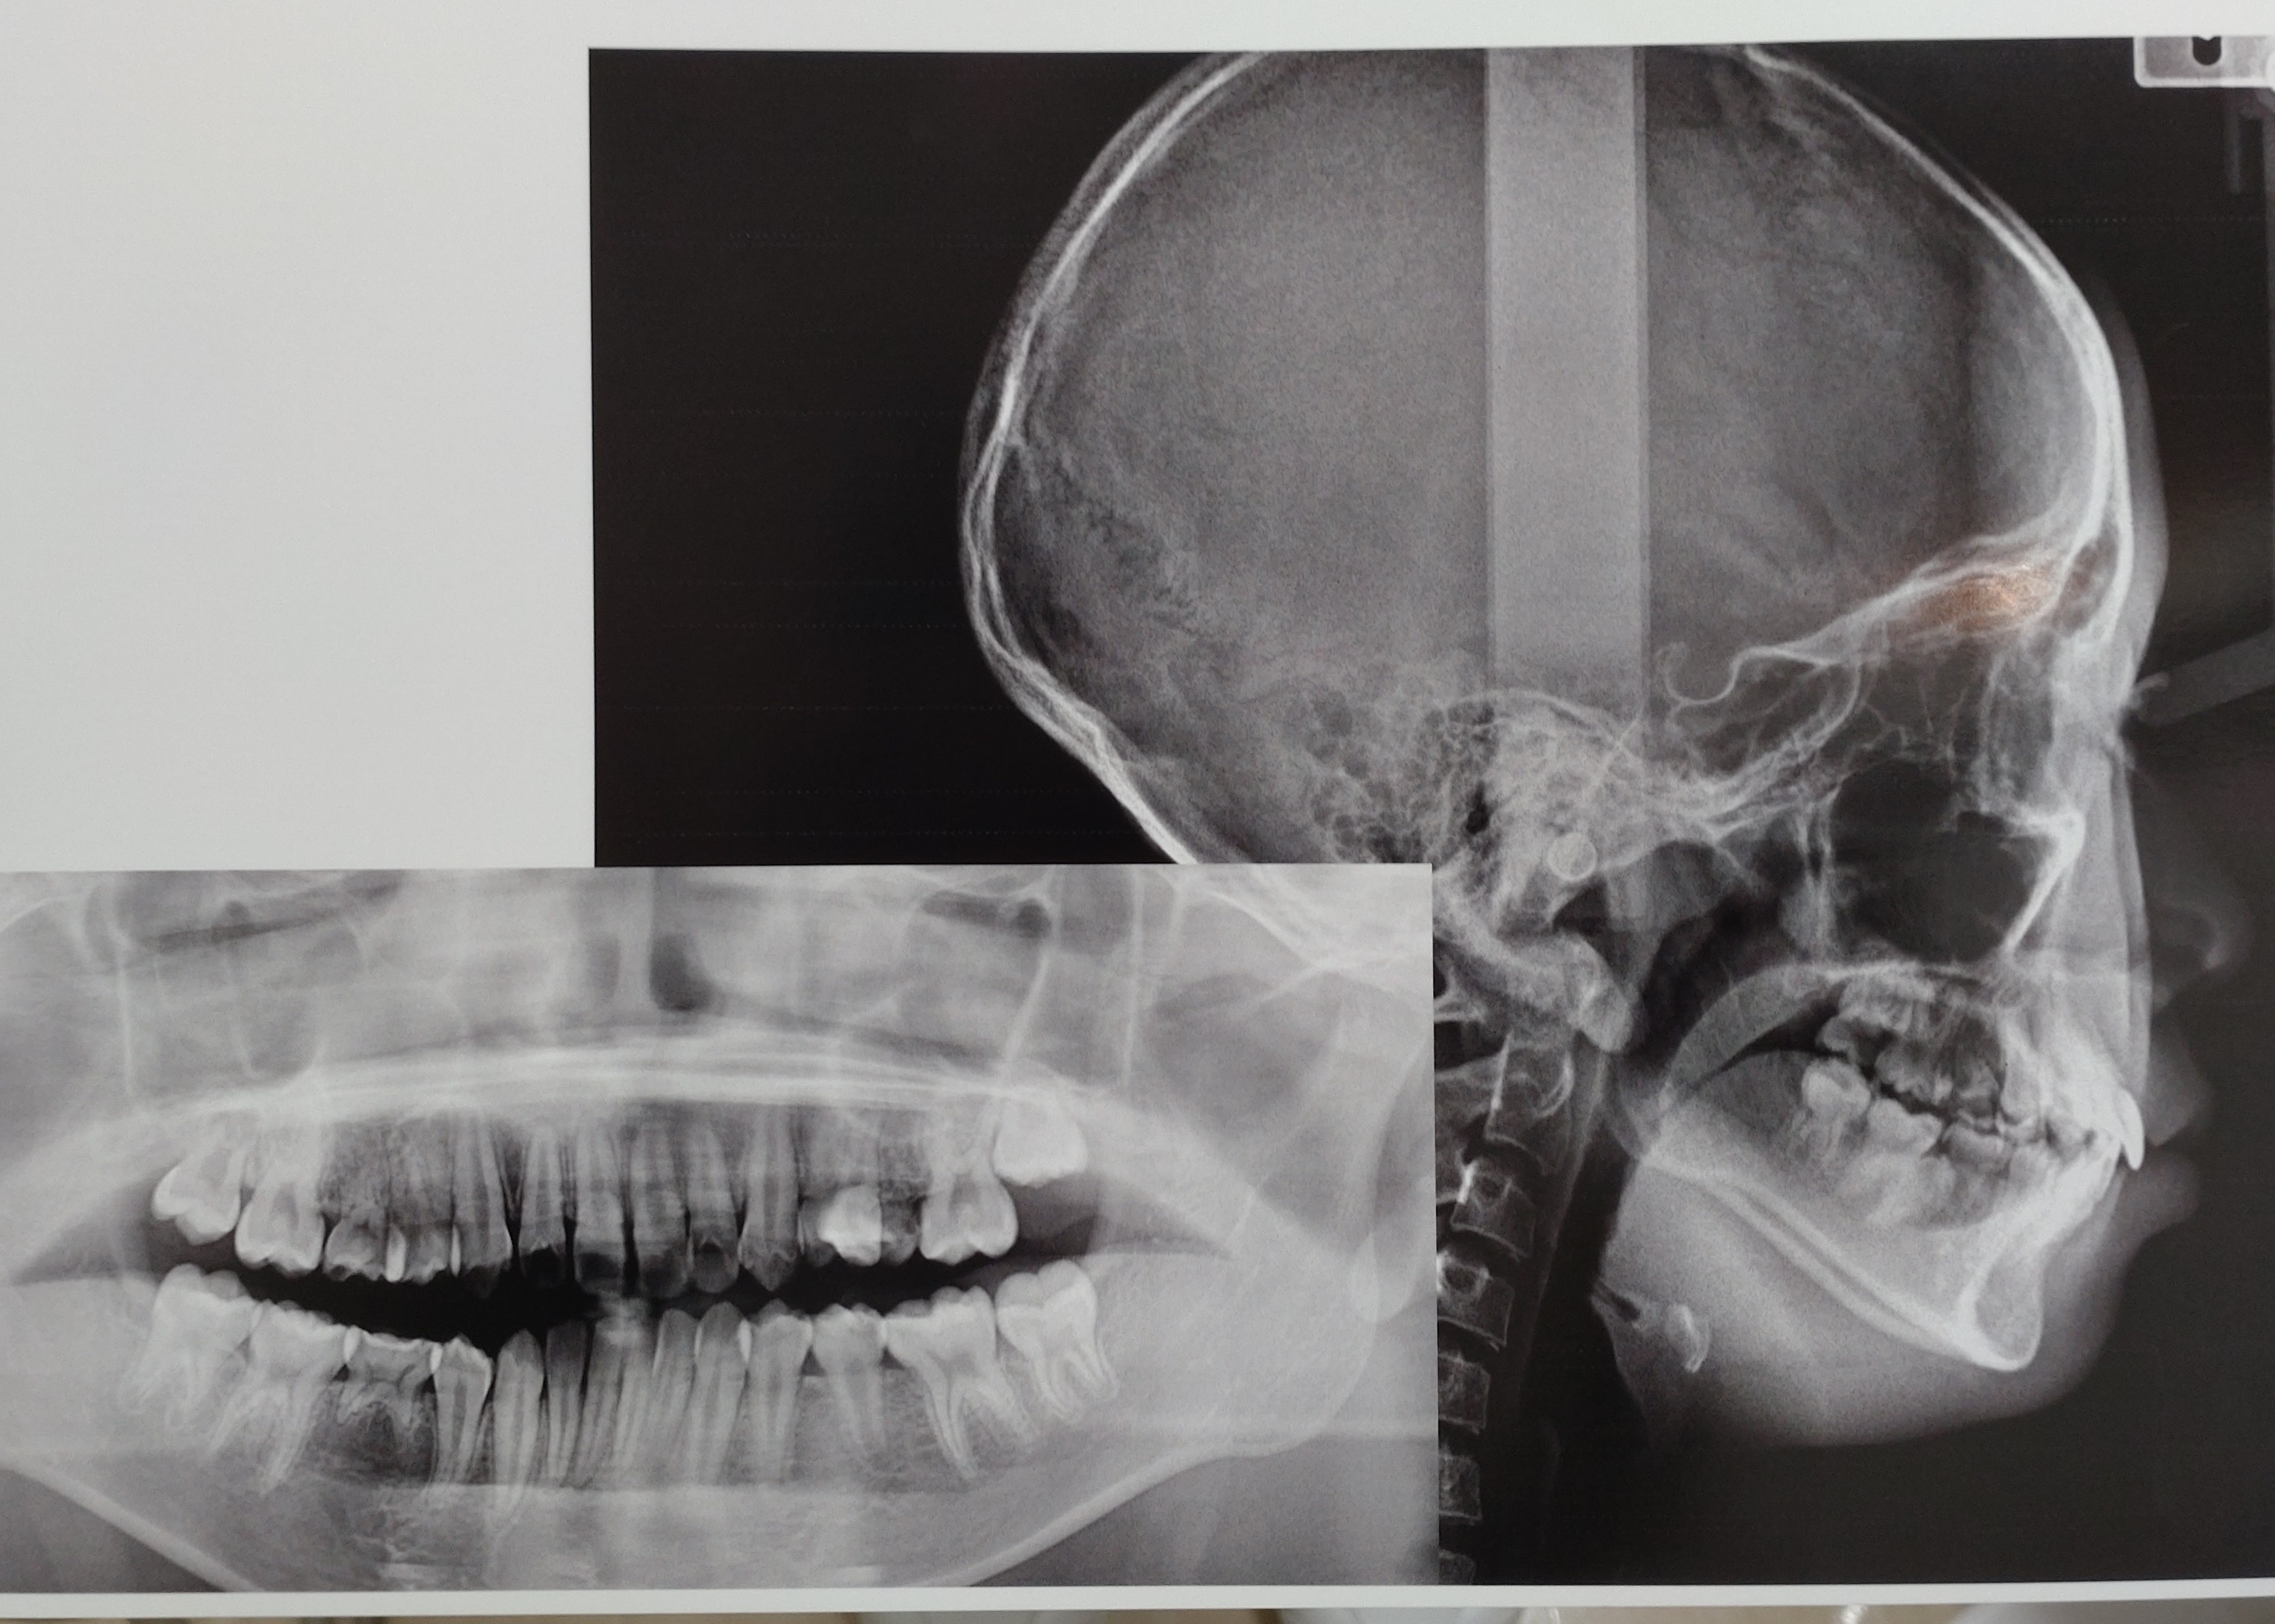

13歳の娘は後続のないEを3本抜歯して矯正する計画で、6番にバンド装着し間もなくEと唯一生え変わった5番1本を抜歯します。

両突歯列

叢生歯列弓(歯と顎の大きさのアンバランス)

左側4番交差咬合

口唇閉鎖時に口腔周囲筋に緊張感

上顎左右5番、下顎右側5番先天性欠損

上顎前歯が大きい

レントゲンを見ると左側7番が手前6番に引っ掛かっているように見えので衛生士さんに言うと

画像1